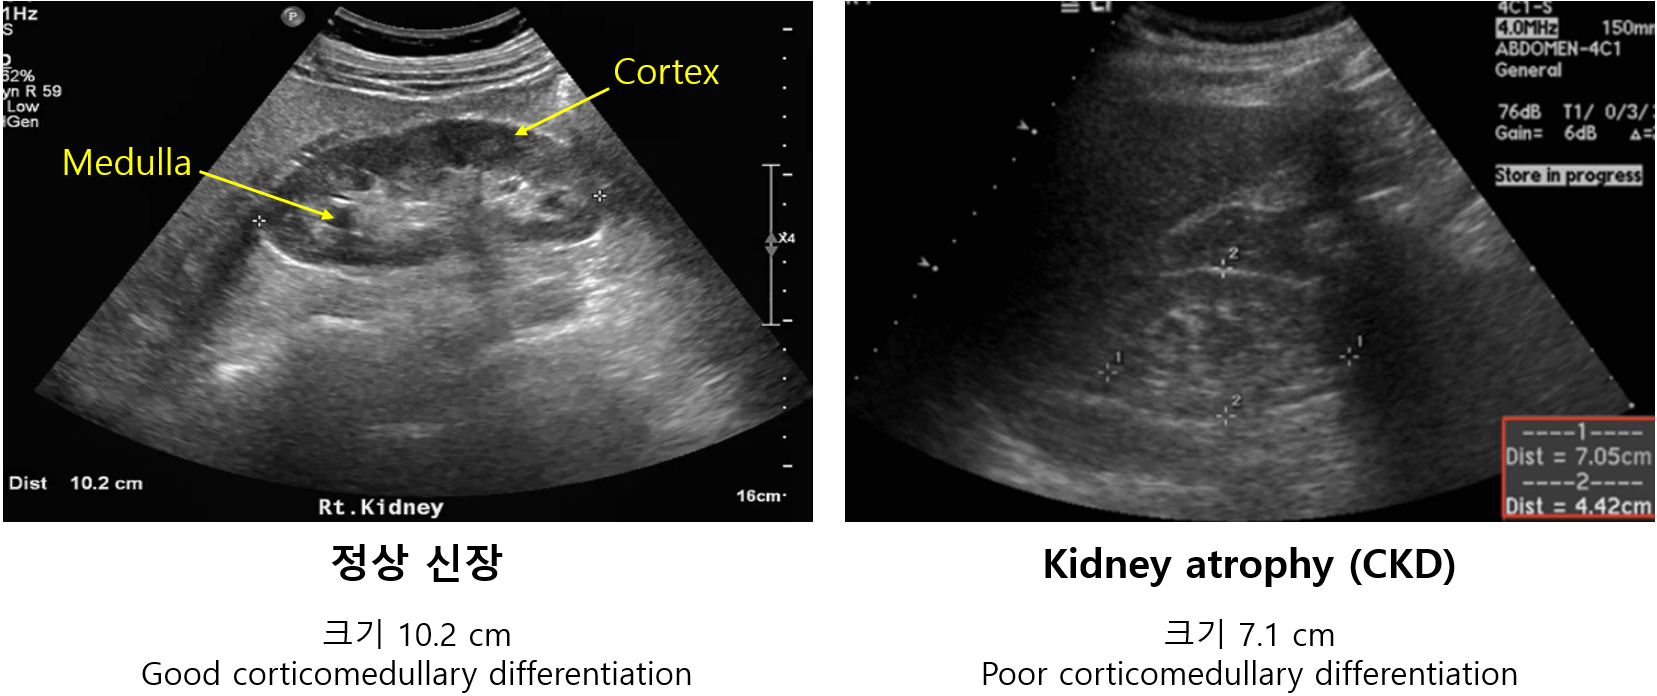

임상적으로 매우 흔한 질환이다. 그만큼 시험에서도 만성 신부전 자체에 대해서도 많이 출제될 뿐만 아니라, 만성 신부전을 동반하는 다양한 질환 및 상태에 대해서도 자주 출제된다. 본 단원은 만성 신부전의 정의, 원인 질환, 진단, staging에 대해 다루고 있다. 만성 신부전의 진단 자체에 대해서는 상대적으로 덜 출제되는 편이지만, 초음파에서 크기가 작아진 양쪽 신장을 보고 만성 신부전임을 알 수 있는지를 묻는 문제가 출제될 수 있다.

2) US: 아래 소견이 확인될 경우 신기능 저하가 '만성'임을 시사함 (AKI와 감별하기)

(1) 양측성 신장 위축(kidney atrophy): < 8~10 cm

* 정상 신장의 크기는 10~14 cm이다. 정상과 kidney atrophy를 구분하는 기준은 문헌마다 조금씩 다르다.

(2) Corticomedullary differentiation: Cortex와 medulla의 echogenicity의 차이가 불분명함

① 정상: Cortex가 medulla 간의 차이가 분명함 (medullary pyramid가 잘 보임)

② CKD: Cortex와 medulla의 음영 경계가 모호해짐